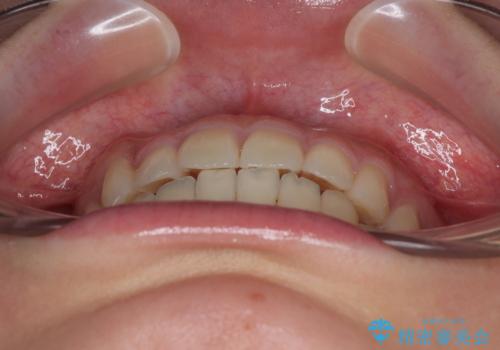

僅か8ヶ月という短期間で、綺麗な歯列に仕上がりました。

- 上下前歯のデコボコを気にして来院された患者様です。